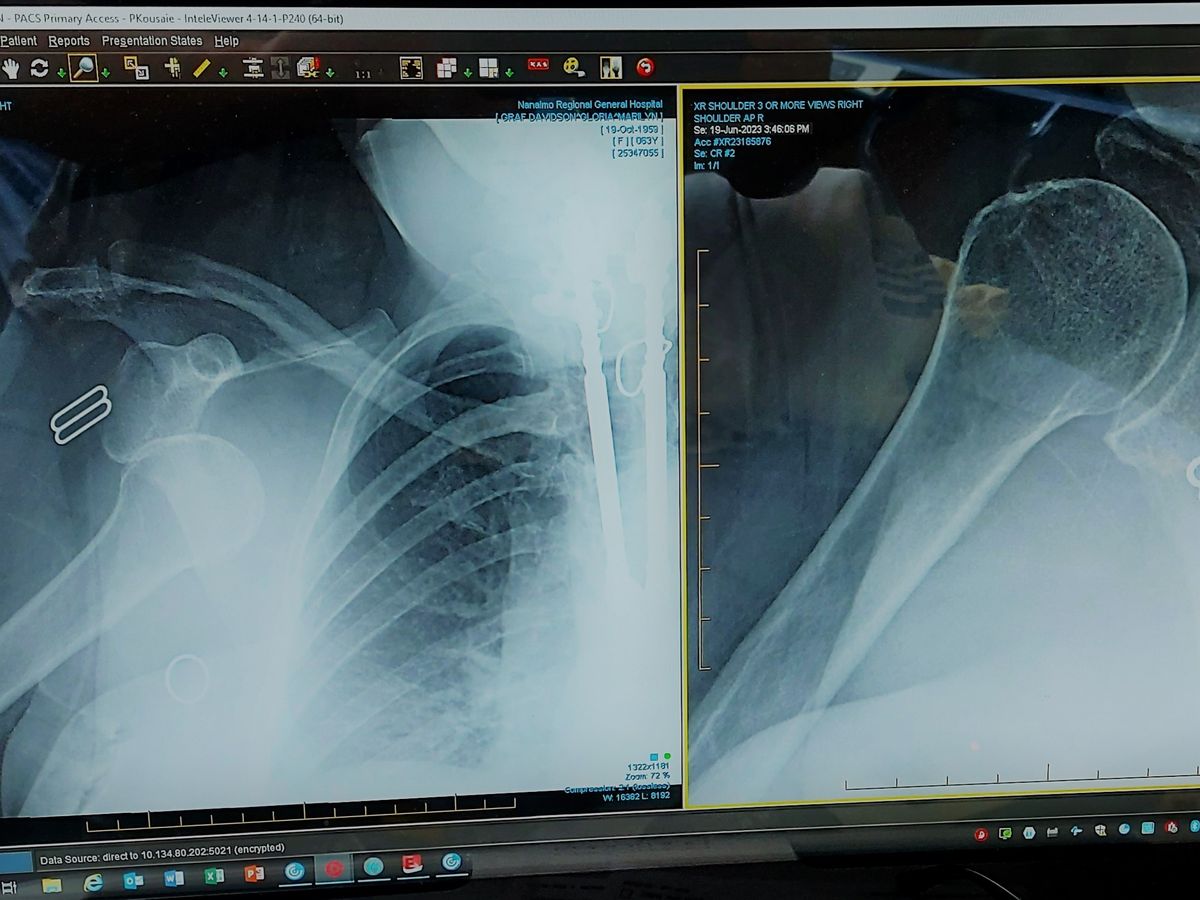

We expect the healing process to be costly and complex due to the fact that she is an incomplete paraplegic. Her spine and legs were partially injured in a car crash, her neck in another crash, and finally her left arm was later injured beyond repair by some incompetent medics. Despite living in constant pain, she always has a smile on her face for everyone and tries her best to make do with what she has. Her right arm is the ONLY limb that functions properly, and currently it has been dislocated-twice!

That's right, after she went to the doctor the first time to get it reset, she also had intense pain in her elbow and returned to emerg the next day. Doctors suspect a fractured elbow. When an MRI was requested, she was asked to put her right arm over her head, and her shoulder dislocated AGAIN! At least the medical staff were profusely apologetic, and my mom, with her gentle nature forgave them. However, to give you an idea of the pain level, my mom said, "I've given birth to three children - I can honestly say this pain was worse."

-dislocated shoulder (twice)

-fractured elbow (likely needs surgery)

-sprained wrist